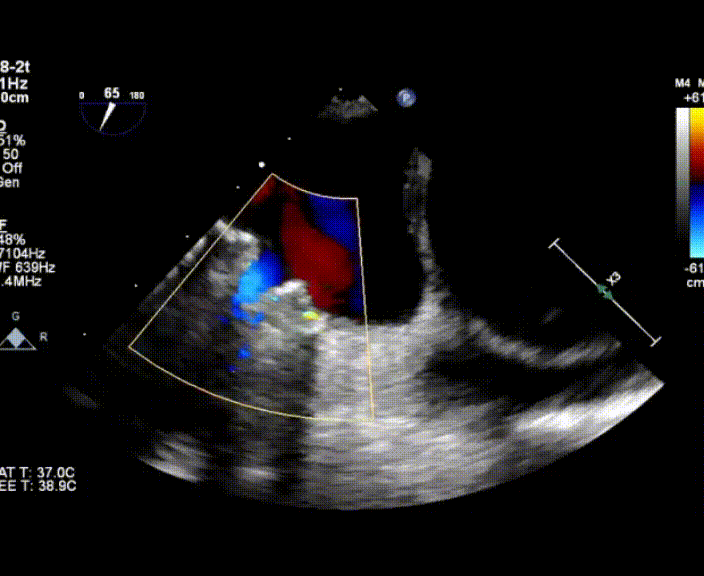

術(shù)中首先在局麻下穿刺股動(dòng)脈、股靜脈,完成心導(dǎo)管檢查評(píng)估后轉(zhuǎn)為全麻,在食道超聲引導(dǎo)下穿刺房間隔,穿刺成功后將加硬導(dǎo)絲送入左上肺靜脈建立軌道,根據(jù)患者病情行球囊預(yù)擴(kuò)張后植入6mm孔徑房間隔造孔支架,經(jīng)透視及食道超聲評(píng)估支架左右盤(pán)展開(kāi)良好,夾持于房間隔兩側(cè),固定穩(wěn)定、位置良好,食道彩超顯示房水平右向左為主分流,分流孔直徑符合預(yù)期大小,心導(dǎo)管檢查評(píng)估達(dá)到預(yù)期效果,釋放造孔支架。術(shù)后12h患者下床活動(dòng),恢復(fù)順利,擬于近日完善術(shù)后評(píng)估后出院。